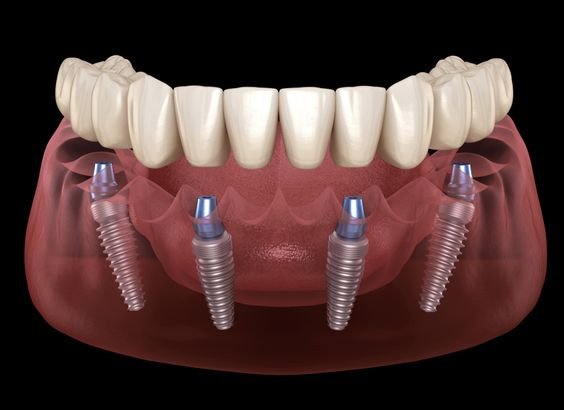

Trồng răng Implant toàn hàm là cách cấy ghép 4 hoặc 6 trụ Implant để thay thế chân răng đã mất, qua đó giúp phục hình hàm răng cho bệnh nhân mất nhiều răng, sắp mất toàn bộ hay mất răng toàn hàm, chủ yếu xảy ra ở giai đoạn trung niên hoặc người cao tuổi. Trong đó, kỹ thuật All-On-4 và All-On-6 thường được sử dụng với nhiều ưu điểm vượt trội: khôi phục khả năng ăn nhai đến hơn 95%, hạn chế các phẫu thuật phức tạp (như ghép xương), cố định, chắc chắn, dễ vệ sinh.

Theo đó, 2 phương án cấy ghép Implant toàn hàm phổ biến là All-On-4 và All-On-6.

- Trồng Implant toàn hàm All-On-4: Là giải pháp cắm 4 trụ Implant trên 1 hàm, thường áp dụng trong trường hợp mất răng hàm dưới. Trong đó, 2 trụ giữa đặt ở vị trí răng trước và 2 trụ hai bên đặt vào vị trí răng sau (răng hàm).

- Trồng răng Implant toàn hàm All-On-6: Giải pháp cắm 6 trụ Implant trên hàm phù hợp cho người có xương hàm quá yếu. Bác sĩ sẽ cắm 4 trụ giữa đặt ở vị trí răng trước và 2 trụ hai bên được đặt ở vị trí răng sau (răng hàm) giúp nâng đỡ răng vững chắc hơn.